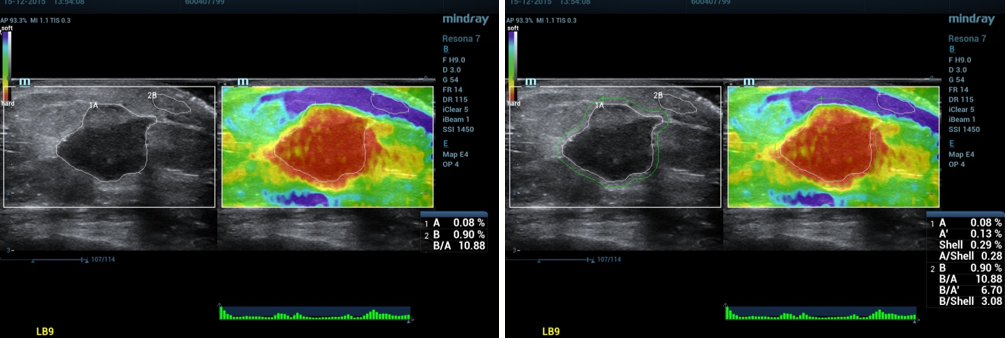

3、数据测量:

①按Measure,选择测量应变比(描记法)。

②分别描记“肿块区域A”和“腺体或脂肪组织”的蓝色区域B,系统自动计算出应变比B/A。

③通过触摸屏shell下的按钮调节Shell大小为2mm(此为多中心研究的诊断标准)。

④系统自动计算出肿块周边区域Shell的应变比B/Shell。

4、正确示范:

(1)乳腺应变式弹性成像(脂肪层出现蓝色带):